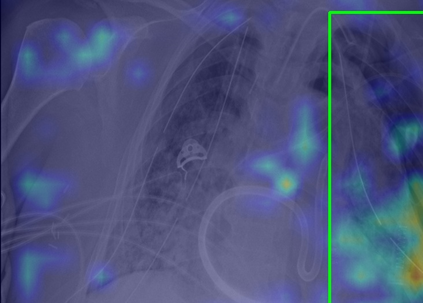

Tuberculosis remains a critical global health issue, particularly in resource-limited and remote areas. Early detection is vital for treatment, yet the lack of skilled radiologists underscores the need for artificial intelligence (AI)-driven screening tools. Developing reliable AI models is challenging due to the necessity for large, high-quality datasets, which are costly to obtain. To tackle this, we propose a teacher--student framework which enhances both disease and symptom detection on chest X-rays by integrating two supervised heads and a self-supervised head. Our model achieves an accuracy of 98.85% for distinguishing between COVID-19, tuberculosis, and normal cases, and a macro-F1 score of 90.09% for multilabel symptom detection, significantly outperforming baselines. The explainability assessments also show the model bases its predictions on relevant anatomical features, demonstrating promise for deployment in clinical screening and triage settings.